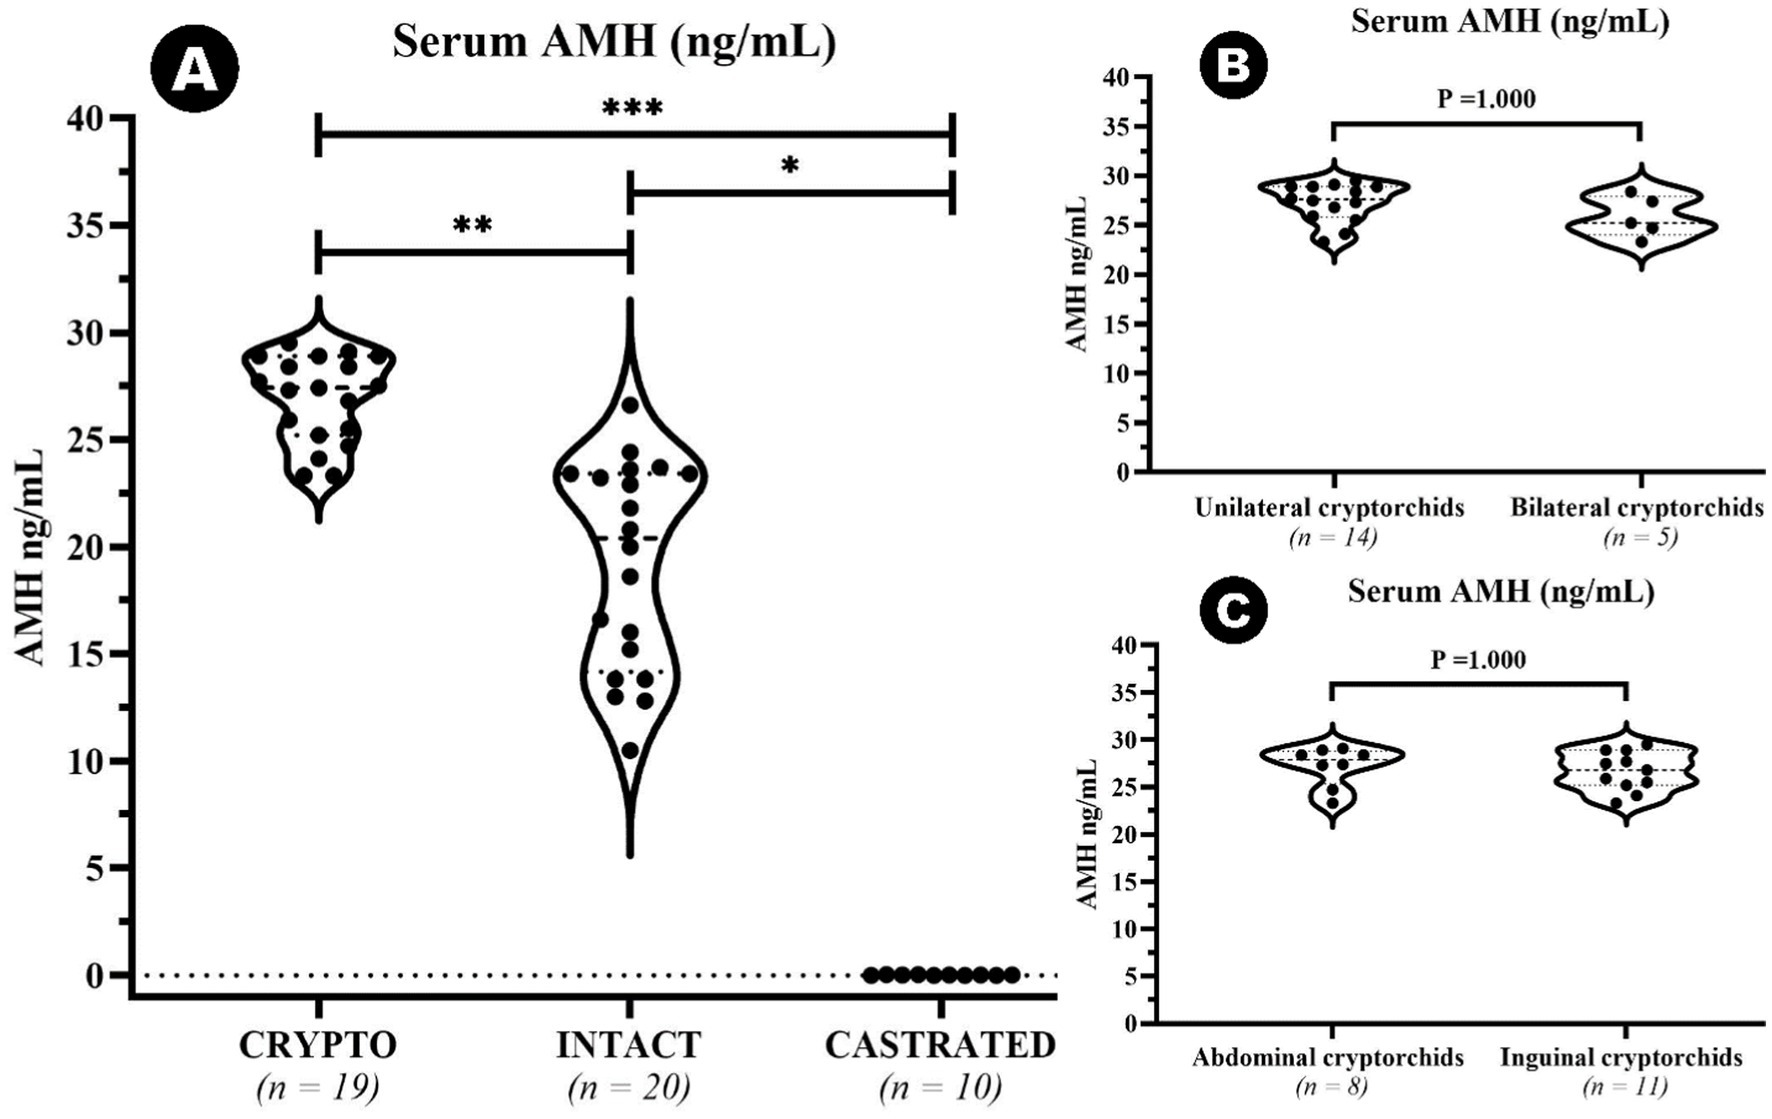

Se identificó un valor atípico en el grupo CRYPTO secundario a los cálculos de IQR. El valor de 10 ng/mL cayó por debajo del límite inferior (15,65 ng/mL) y, por lo tanto, se excluyó del análisis posterior. El resto de los datos sobre los niveles séricos de AMH mostraron diferencias significativas entre grupos específicos (Figura 2). El grupo CRYPTO tuvo niveles significativamente más altos de AMH (n = 19; mediana 27,4 ng/mL, IQR = 3,7) en comparación con los grupos INTACT (n = 20; mediana 20,4, IQR 9,25, p ≤ 0,01) y CASTRADOS (n = 10; 0,01 ± 0,01 ng/mL, p ≤ 0,001) (Figura 2A). Los sujetos del grupo CASTRATED (n = 20) mostraron solo valores séricos de AMH por debajo del límite de detección descrito del kit, lo que también provocó una diferencia significativa en comparación con los niveles séricos de AMH INTACT. Sin embargo, no se detectaron diferencias significativas entre las criptorquídeas unilaterales y bilaterales (p = 1.000) (Figura 2B), ni entre las criptorquídeas abdominales e inguinales (p = 1.000) (Figura 2C). Después de excluir el valor atípico en los valores de AMH, la mediana de edad en todos los grupos fue de 24 meses (n = 49, IQR = 27). No se observaron diferencias estadísticamente significativas en la distribución por edades entre los grupos CRYPTO, CASTRAED e INTACT p ≥ 0,05. En particular, se detectó una correlación negativa entre la edad y los niveles de AMH en todos los grupos (ρ = −0,415, p ≤ 0,01). Sin embargo, al calcular el análisis excluyendo a los individuos castrados, que suelen tener niveles bajos de AMH independientemente de la edad, la correlación entre la edad y los valores de AMH siguió siendo negativa (ρ = −0,223) pero ya no fue estadísticamente significativa (p ≥ 0,05) (Figura 3A). Además, cuando se investigó la relación entre la edad y los niveles séricos de AMH dentro de los grupos de edad separados, se identificó una correlación negativa entre las dos variables en perros menores de 24 meses (ρ = −0,461, p < 0,05) (Figura 3B). Por el contrario, esta correlación no fue significativa en la categoría de adultos (≥25 meses) (ρ = −0,108, p ≥ 0,05) (Figura 3C).